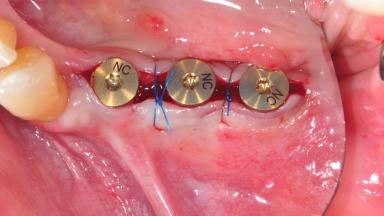

After the placement of three diameter-reduced two-piece implants the bone is augmented with autologous bone chips and DBBM particles to enlarge the crest volume. The surgery is completed with the application of two membrane layers and primary wound closure.

For soft tissue management, the initial healing caps are replaced with a longer type 8 weeks after implant placement in a second intervention before prosthodontic treatment is initiated.

The case concludes with the presentation of the final prostheses at the 3-year follow-up, demonstrating a stable and pleasing soft- and hard-tissue situation.